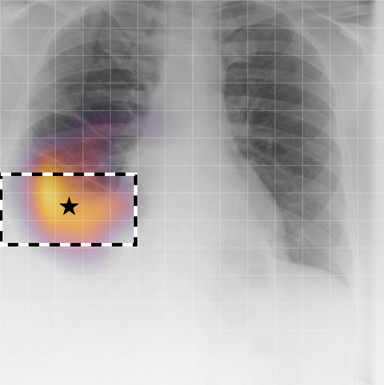

| (1) |

for , where denotes 2D sinusoidal positional encodings [12] and is its temporal counterpart, which is learnt (Fig. 2) [4]. The layer-normalised () [6] output of the final transformer encoder block is an ‘aggregated’ representation of patch-level progression information anchored on the current image. Figure 3 shows attention roll-out [1] applied to after pre-training, showing how the prior image contributes to the fused representation. Figure A.5 further highlights the robustness to variations in pose underlining that registration is not necessary for this encoder.

A.3 Self-attention visualisation

In Figure A.3, we show examples of self-attention rollout [1] maps for pleural effusion and consolidation, including radiologist-annotated bounding boxes surrounding the corresponding pathology in each prior and current image.

To model the attention flow through the transformer encoder block, we first average each attention weight matrix across all heads, subsequently we multiply the matrices between every two layers. For every block we add the identity matrix in order to model the residual connections. Last, we only keep the top 10 of attention weights per block to reduce noise in the final rollout map. In contrast to [21], we do not visualize the rollout map with respect to a [CLS] token. Instead, we choose a reference image patch from the center of the radiologist-annotated bounding boxes, marked with in Figure A.3.

We find that the rollout maps in Figure A.3 are in good agreement with radiologist-annotated bounding boxes, i.e., the reference patch attends to other patches within the bounding boxes in the prior and current image. In addition, we find that BioViL-T is robust to pose variations, e.g., in Figure A.3 (a) we show that despite the vertical shift between prior and current image, the reference patch attends to the correct image patches in the prior image.